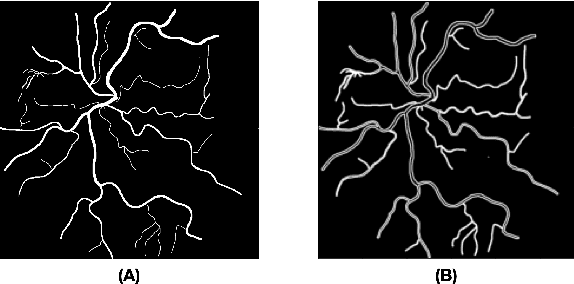

Abstract:The retina is the only part of the human body in which blood vessels can be accessed non-invasively using imaging techniques such as digital fundus images (DFI). The spatial distribution of the retinal microvasculature may change with cardiovascular diseases and thus the eyes may be regarded as a window to our hearts. Computerized segmentation of the retinal arterioles and venules (A/V) is essential for automated microvasculature analysis. Using active learning, we created a new DFI dataset containing 240 crowd-sourced manual A/V segmentations performed by fifteen medical students and reviewed by an ophthalmologist, and developed LUNet, a novel deep learning architecture for high resolution A/V segmentation. LUNet architecture includes a double dilated convolutional block that aims to enhance the receptive field of the model and reduce its parameter count. Furthermore, LUNet has a long tail that operates at high resolution to refine the segmentation. The custom loss function emphasizes the continuity of the blood vessels. LUNet is shown to significantly outperform two state-of-the-art segmentation algorithms on the local test set as well as on four external test sets simulating distribution shifts across ethnicity, comorbidities, and annotators. We make the newly created dataset open access (upon publication).

Abstract:Introduction: Blood vessels can be non-invasively visualized from a digital fundus image (DFI). Several studies have shown an association between cardiovascular risk and vascular features obtained from DFI. Recent advances in computer vision and image segmentation enable automatising DFI blood vessel segmentation. There is a need for a resource that can automatically compute digital vasculature biomarkers (VBM) from these segmented DFI. Methods: In this paper, we introduce a Python Vasculature BioMarker toolbox, denoted PVBM. A total of 11 VBMs were implemented. In particular, we introduce new algorithmic methods to estimate tortuosity and branching angles. Using PVBM, and as a proof of usability, we analyze geometric vascular differences between glaucomatous patients and healthy controls. Results: We built a fully automated vasculature biomarker toolbox based on DFI segmentations and provided a proof of usability to characterize the vascular changes in glaucoma. For arterioles and venules, all biomarkers were significant and lower in glaucoma patients compared to healthy controls except for tortuosity, venular singularity length and venular branching angles. Conclusion: We have automated the computation of 11 VBMs from retinal blood vessel segmentation. The PVBM toolbox is made open source under a GNU GPL 3 license and is available on physiozoo.com (following publication).